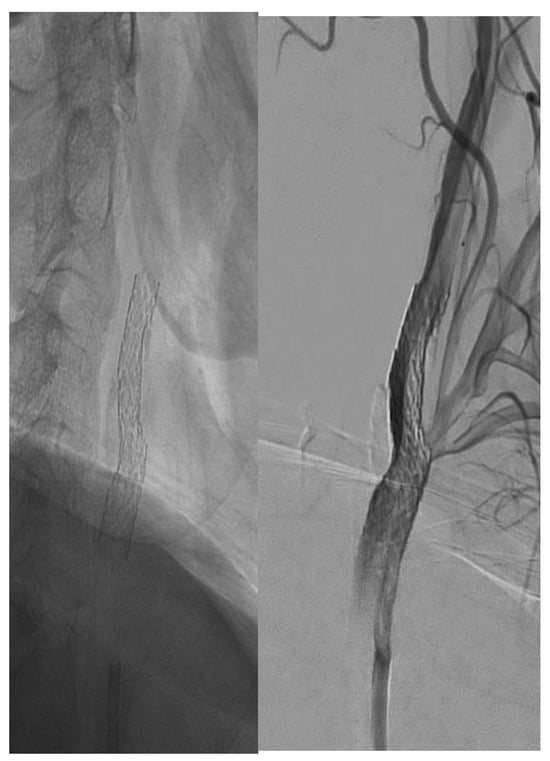

Visual differences between single- and double-layer carotid stents as seen during the angiography procedure are illustrated in Figure 2, Figure 3 and Figure 4.

Figure 3. Double-layer micromesh stent (Cguard-Inspire MD).

Jcm 14 00888 g003